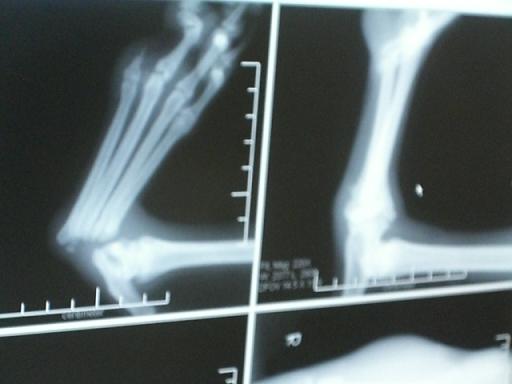

たぶん交通事故か何かで左後ろ足小指を失い、その勢いで一気に全部の指が付け根から脱臼しています。

獣医師さんの見解では、おそらく半年くらい前の怪我で、すでに失った骨のかわりに、普通は地につけない

部分をうまく使い、そこにタコができて歩行しています。